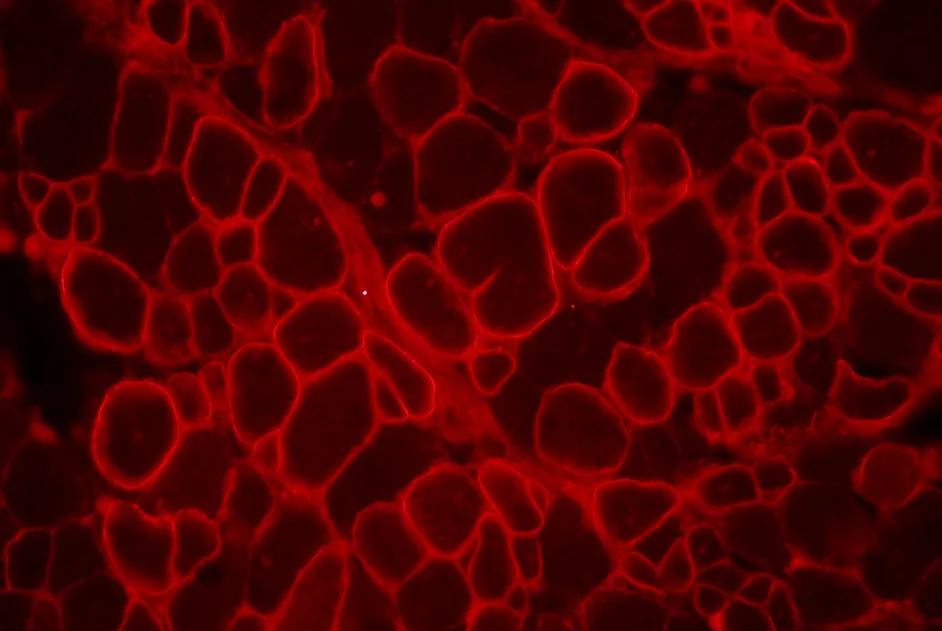

Myopathie FSH : FRG1 régule la différenciation musculaire des souris

Une équipe germano-italienne a montré que la protéine FRG1 interagit avec une enzyme, Suv4-20h1, et inhibe la différenciation musculaire.